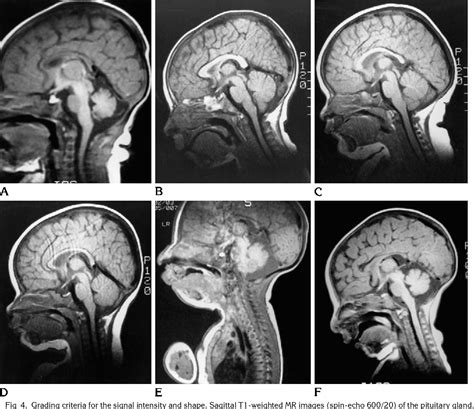

During a Pituitary Gland MRI, patients lie on a table that slides into a large, cylindrical machine. The MRI machine uses magnetic fields and radio waves to produce detailed images of the pituitary gland. The procedure typically takes about 30 to 60 minutes, depending on the complexity of the scan. Patients may be asked to lie still and hold their breath for short periods to ensure clear images. In some cases, a contrast agent may be injected to enhance the visibility of certain structures.

Interpreting Pituitary Gland MRI Results

Interpreting the results of a Pituitary Gland MRI involves analyzing the images to identify any abnormalities, tumors, or other conditions that may affect the pituitary gland. Healthcare professionals look for: